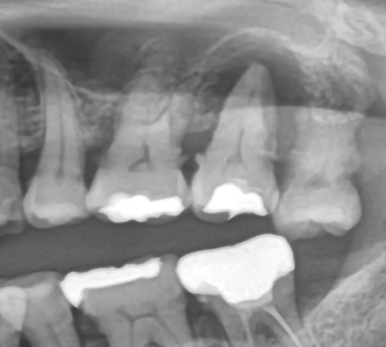

1. 치아가 세로로 금 간 경우 (수직 파절)

치아가 세로로 갈라지는 ‘수직 파절’은

신경치료를 하더라도 예후가 좋지 않습니다.

금이 간 틈으로 세균이 침투하면

잇몸뼈까지 염증이 퍼지며 결국 발치가 불가피해요.

👉 파절 부위가 잇몸 아래까지 도달한 경우, 빠른 판단이 필요합니다.